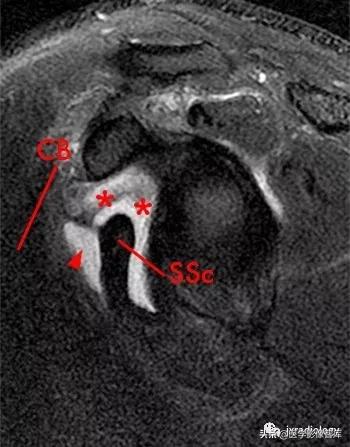

星号:superior subscapularis recess:肩胛下肌上隐窝

箭头:subcoracoid bursa:喙突下滑囊

SSc:肩胛下肌腱

小箭:middle glenohumeral ligament :盂肱中韧带

CB:喙肱肌和肌腱